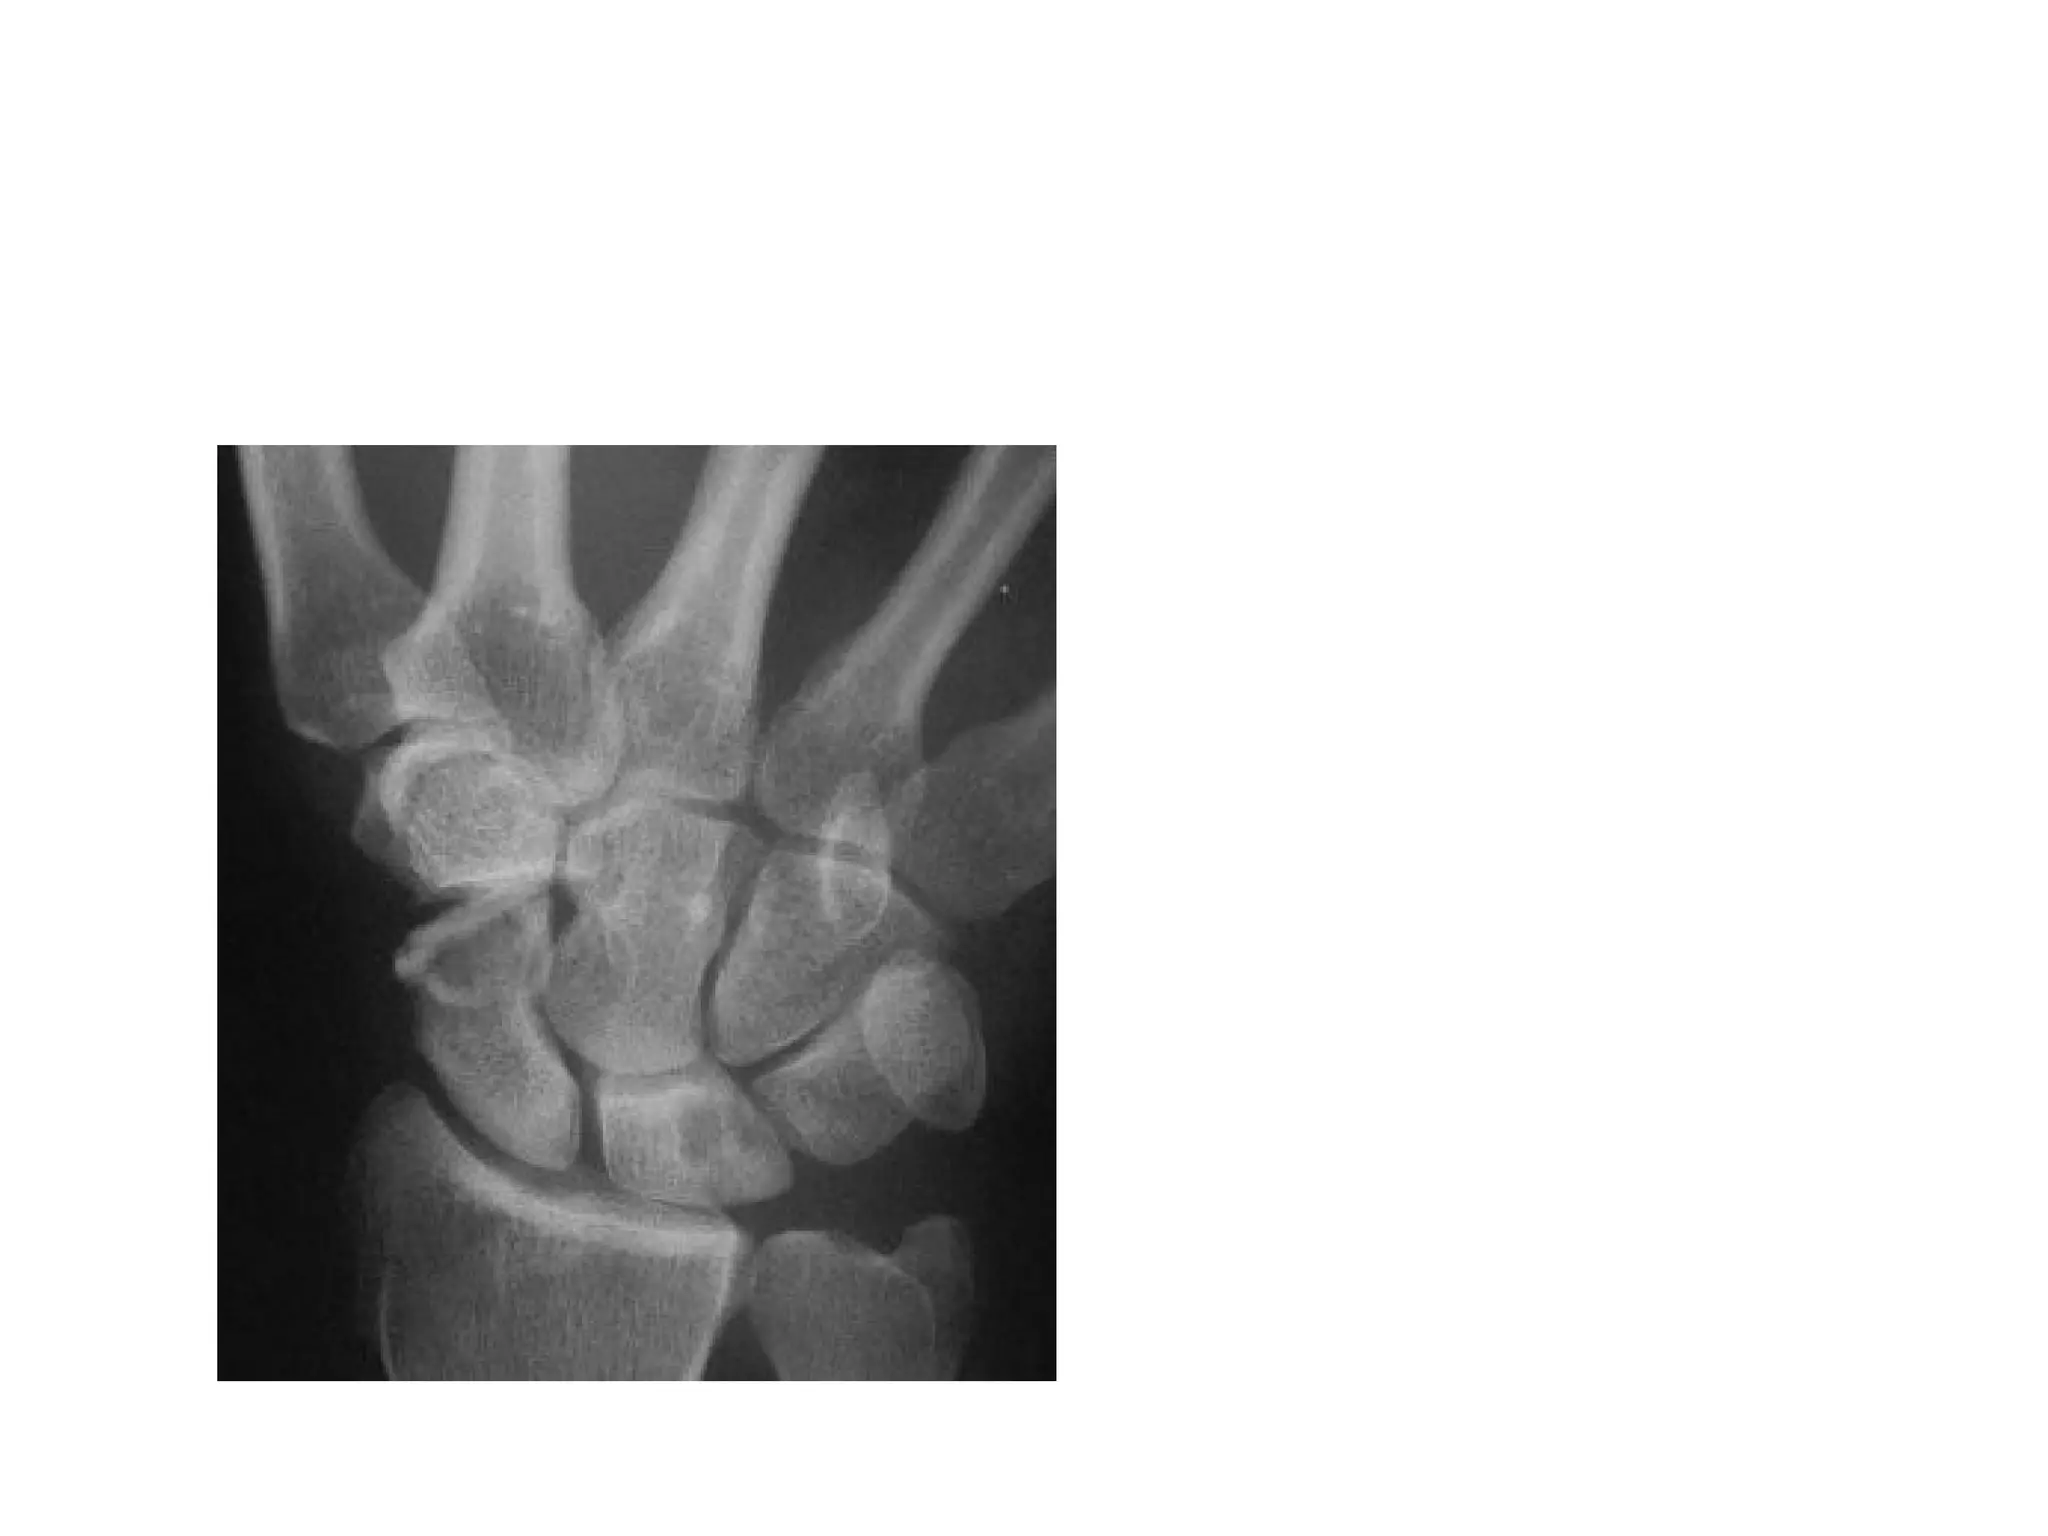

Wrist PA

Suggested by: • patient’sage, • mechanism of injury • signs and symptoms Imaging • Xray….Can miss 20%of # • CT Scan-for staging & if plain flims normal • MRI-most sensitive test(within 24hrs with pain) • Bone Scan (3-4days)-100% SENSITIVE

• #9 1.PA 2.LATERAL 3.SCAPHOID VIEW…WRIST EXTENSION 30 DEGREE & ULNAR DEVIATION 20 DEGREE 4.SUPINATED OBLIQUE OTHERS PRONATED OBLIQUE

• #10 IMAGING OF CHOICE SCAPHOID VIEW ……